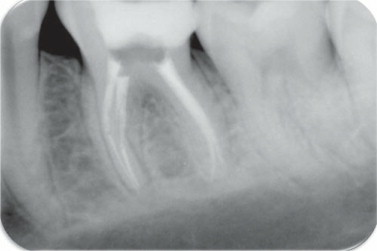

En 1899, -y gracias al descubrimiento de los rayos X por Roentgen 1,895- Kells usaba las radiografías para medir la longitud de los dientes durante la terapéutica de conductos radiculares. Un año después, en 1900, el Dr. Weston A. Prize sugirió que las radiografías se utilizaran para verificar la calidad de las obturaciones de los conductos radiculares.